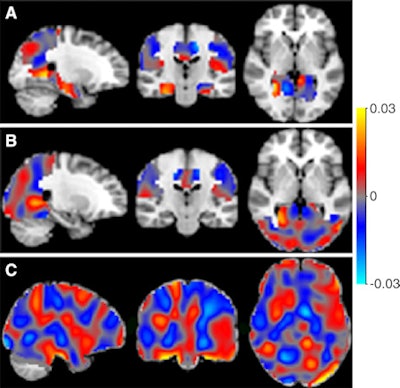

A research team led by Alle Meije Wink, PhD, from VU University Medical Center Amsterdam used machine-learning techniques to analyze arterial spin-labeled (ASL) MRI scans, which create perfusion maps that depict blood flow to various regions of the brain. A machine-learning application was trained to recognize patterns in the maps to distinguish between patients with varying levels of cognitive impairment and to predict the stage of Alzheimer's disease cases that were not yet diagnosed (Radiology, July 6, 2016).

The researchers then analyzed images using an open-access software platform, Pattern Recognition for Neuroimaging Toolbox (Pronto), which enables multivariate analysis of neuroimaging data based on machine learning.

The Pronto application was able to differentiate between individuals with Alzheimer's disease, MCI, and SCD, the researchers reported. It was also able to predict the prognosis of patients with accuracy ranging from 82% to 90%, leading Wink et al to conclude that ASL is a "promising alternative functional biomarker" for the early diagnosis of Alzheimer's disease.